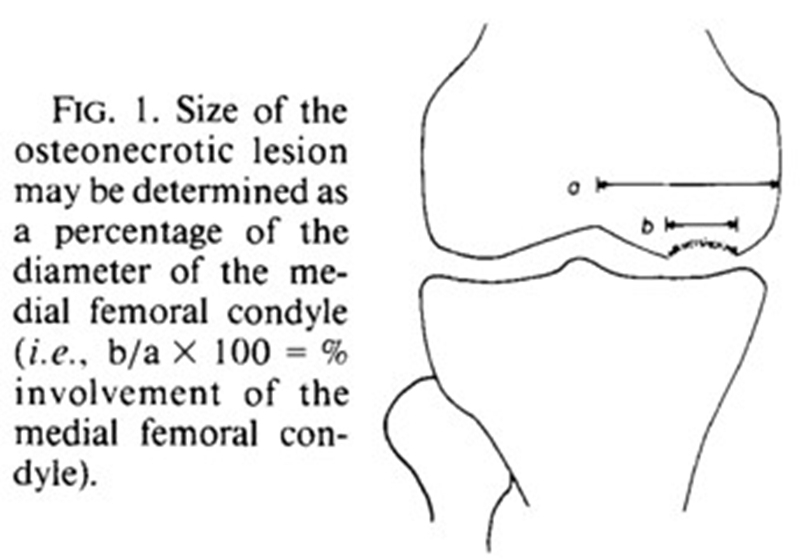

X线+MRI:通过测量正位X线片和MRI判断坏死区域的大小。

关于影像学评估与SONK的预后的关系,多项研究表明小于3.5cm2的小坏死病变可进行保守治疗,在冠状位X片上5cm2软骨下病变面积作为预测预后不良和高风险进展的临界值,前后位X片坏死区>50%髁,会迅速塌陷,病变范围很大(>40%髁/前后位X 片)或有早期骨关节炎的影像表现,保守欠佳。

早期(3月内)内侧半月板相对挤压百分比≥33%,是SONK发病1年后预后不良的预测指标,MRI检查没有局灶性轮廓塌陷和髁深处没有低信号线(隔离带),预后好,股胫角>180°(下肢力线内翻>6°)和MRI上深度>20mm 预示SONK患者症状发作后1年预后不良。

内侧半月板挤压(MME)以绝对值和挤压相对百分比 (RPE) 的形式呈现,其定义为挤压半月板宽度与整个半月板宽度相比的百分比